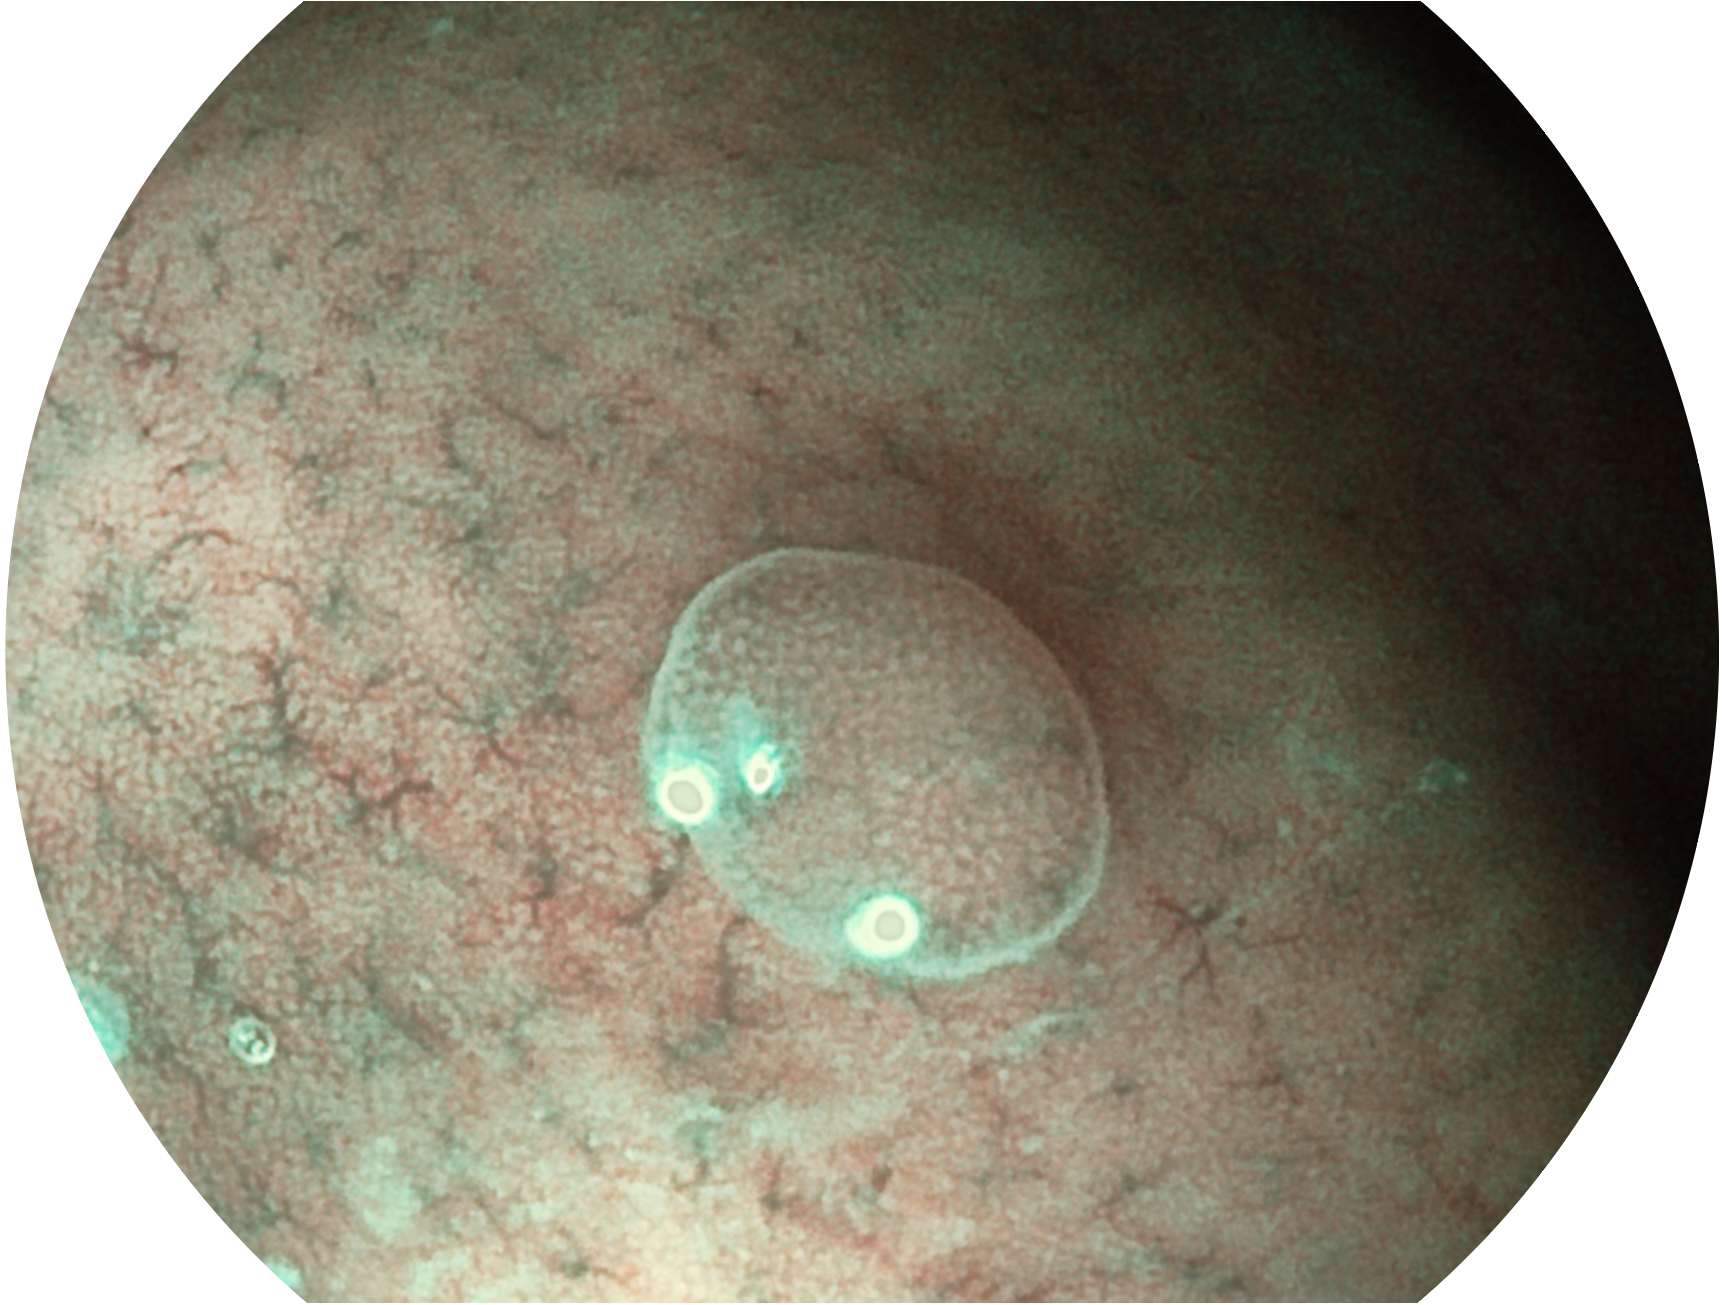

百老汇电子游戏官网新开发的内镜染色技术,主要是基于多波长LED 光源的开发,VLS-55Q 四波长LED 光源是由四个不同颜色的LED光按照相应照明模式所规定的特定发光比例进行合束后形成,合束后形成的照明光的光谱由红光、绿光、蓝光及蓝紫光这四个不同的波段范围构成。具有更高光谱自由度,通过光谱比例的控制,实现了聚谱成像技术,英文全称为“Spectral Focused Imaging, SFI”,缩写为“SFI”和光电复合染色成像技术,英文全称为“Versatile Intelligent Staining Technology, VIST”,缩写为“VIST”。